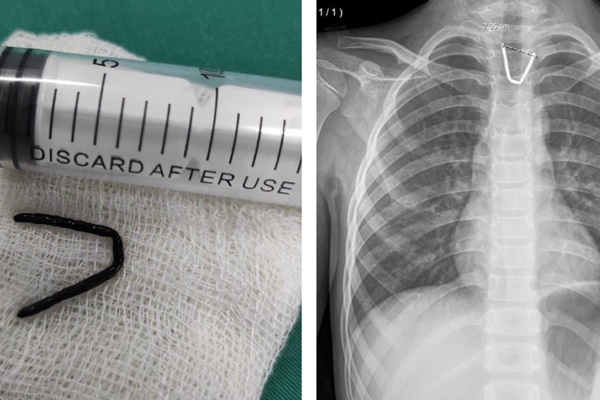

Hình ảnh dị vật bị mắc trong thực quản của bệnh nhi.

Qua thăm khám và kết quả chụp X-quang, các bác sĩ xác định dị vật là đoạn kim khí hình chữ U, cạnh dài nhất 2 cm, đầu sắc nhọn, vị trí tương ứng đoạn 1/3 trên thực quản.

Sau khi hội chẩn, các bác sĩ đã tiến hành lấy dị vật bằng phương pháp nội soi thực quản bằng ống mềm có gây mê. Sau hơn 30 phút, dị vật được lấy ra thành công, đảm bảo an toàn cho bệnh nhi.